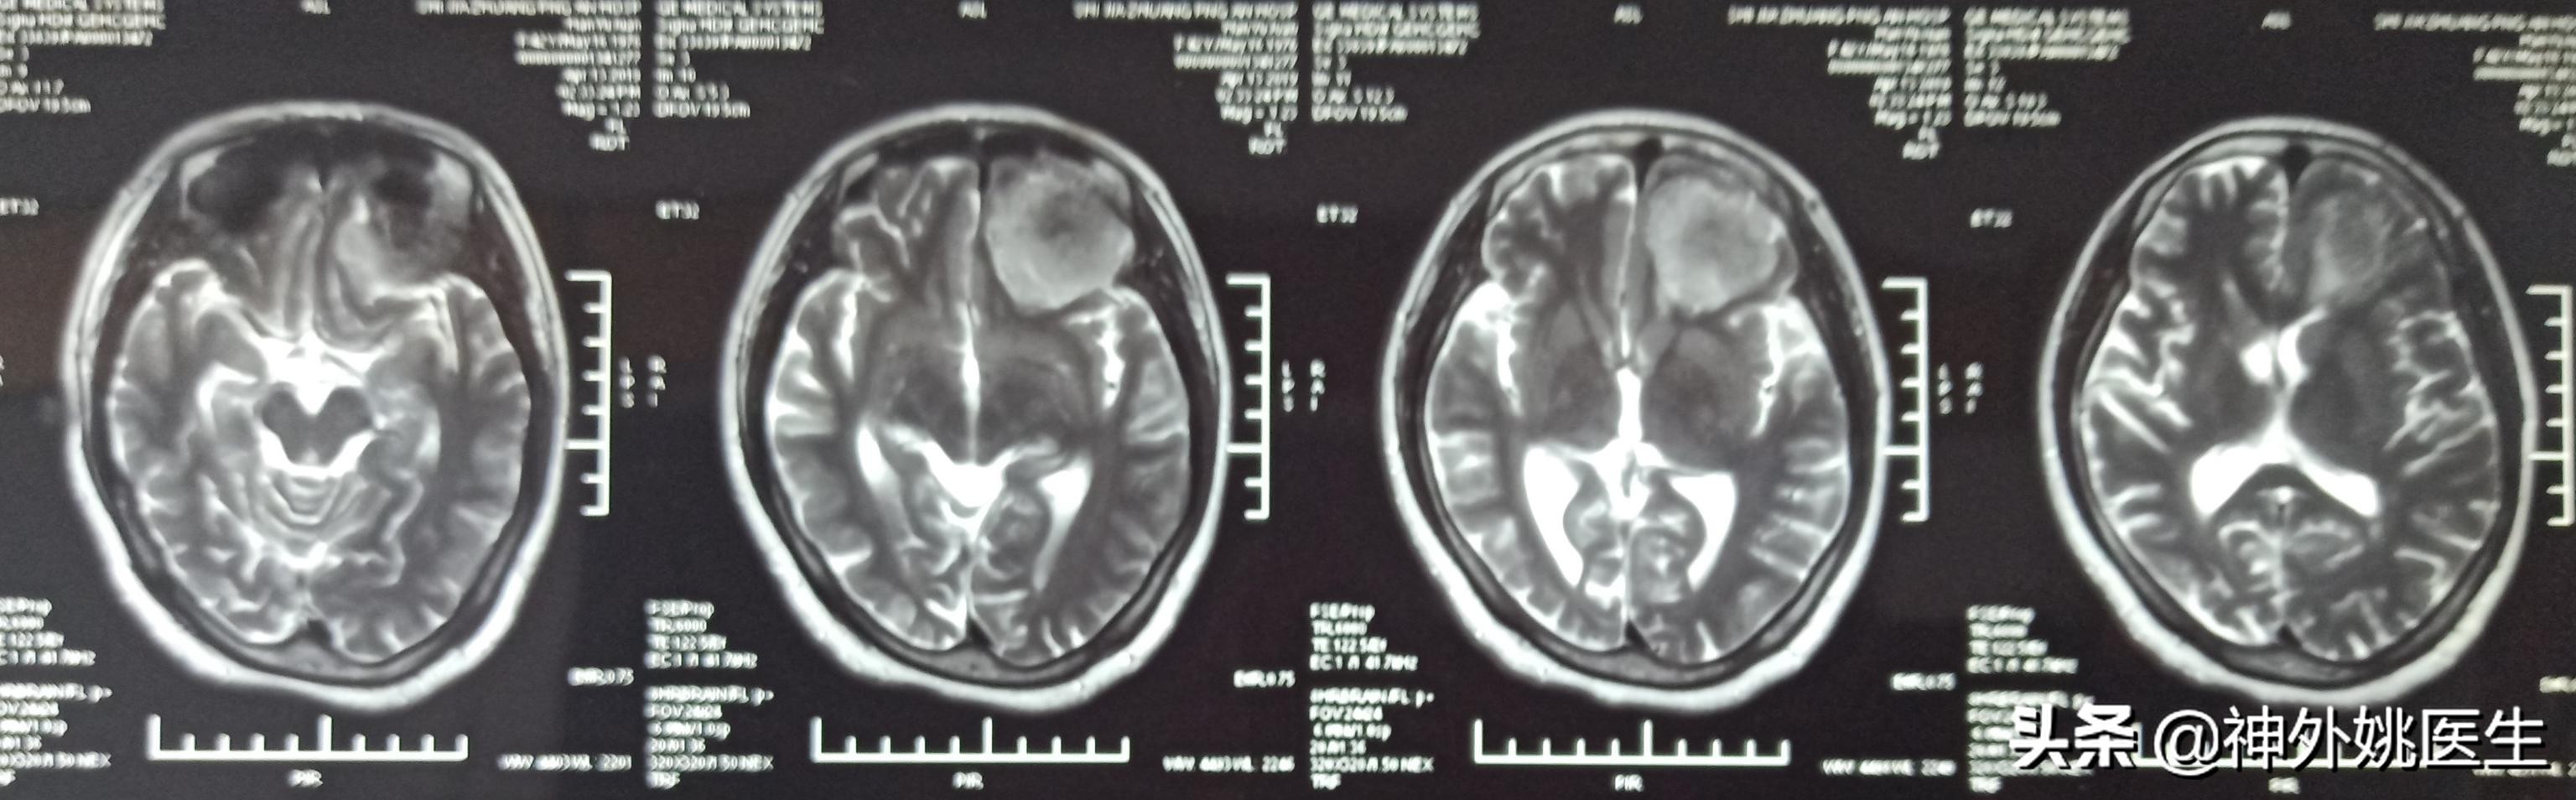

头MRI检查:1、左额部脑膜瘤。2、左侧放射冠区腔隙性脑梗死。(图3-7)

图5 T2Flair像病变呈稍高T2信号。

图6 增强扫描可见病变呈不均匀强化。

图7 病变基底位于颅底硬膜,可见脑膜尾征,病变大小约3.8cm x 4.1cm x 2.9cm。